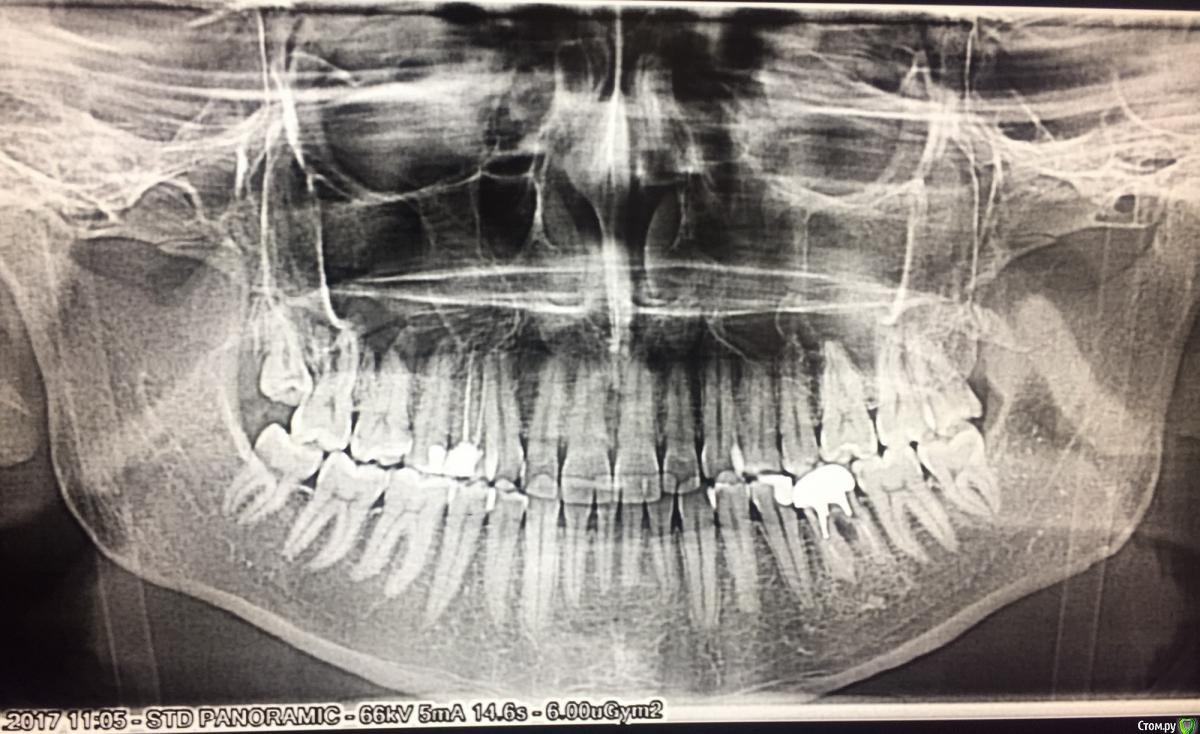

Jackfor18 Опубликовано 6 марта, 2018 Поделиться Опубликовано 6 марта, 2018 Помогите!!!!!!! Друзья, помогите пожалуйста определиться с диазнозом и с вариантами лечения !!!!! Я запутался, а к тем врачам что я ходил, думаю лукавят и не вызывают доверия. Прикус медиальный, но при это нижняя челюсть (подбородок мал)?! Верхняя челюсть при этом крупнее нижней, и всё равно её нужно расширять? Аппарат Дерихсвайлера ? Или оперировать нижнюю челюсть?Друзья, подскжаите советом, голова кругом. Какие варианты лечения?Поможет ли брейкет система? И все таки непонятно какой у меня диагноз до сих пор не разберусь? Заранее спасибо! Ссылка на комментарий